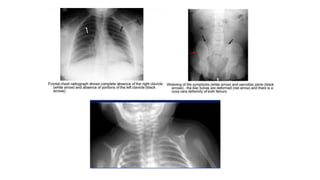

Cleidocranial dysplasia. Radiographs of skull (A, B) show open fontanelles and wormian bones

(arrows, A) and hot cross bone appearance (arrow, B).

Radiograph of chest(C) shows hypoplastic right clavicle (arrow). Radiograph of hand (D) shows elongated

second digit with an accessory epiphyseal centre (arrow) Radiograph of pelvis (E) shows “chef-hat” shaped

femoral heads (arrow) and widened pubis symphysis.

(2) The clavicles are either absent (10%) or hypoplastic (90%), hypoplasia

affecting the lateral ends more than middle or medial ends. Also the

scapulae may be small and thoracic cage cone-shaped;

(3) In hands and feet, the 2nd digit is elongated due to presence of

accessory epiphyses for the second metacarpal while the distal phalanges

are small and pointed; and

(4) The pelvis is small with widened symphysis pubis and abnormal shape

of femoral heads called “chef-hat” appearance.